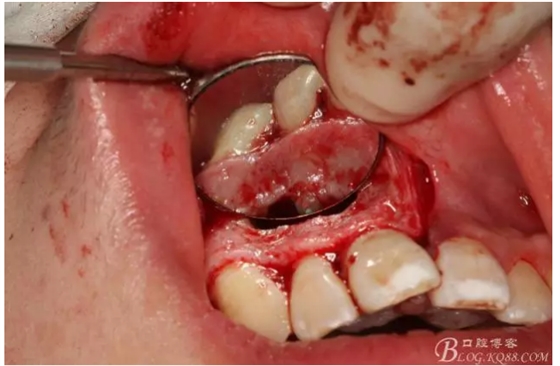

圖4.摘除囊壁后形成的巨大骨腔

圖5.清理骨腔,可以看到12的根尖暴露在骨腔內。